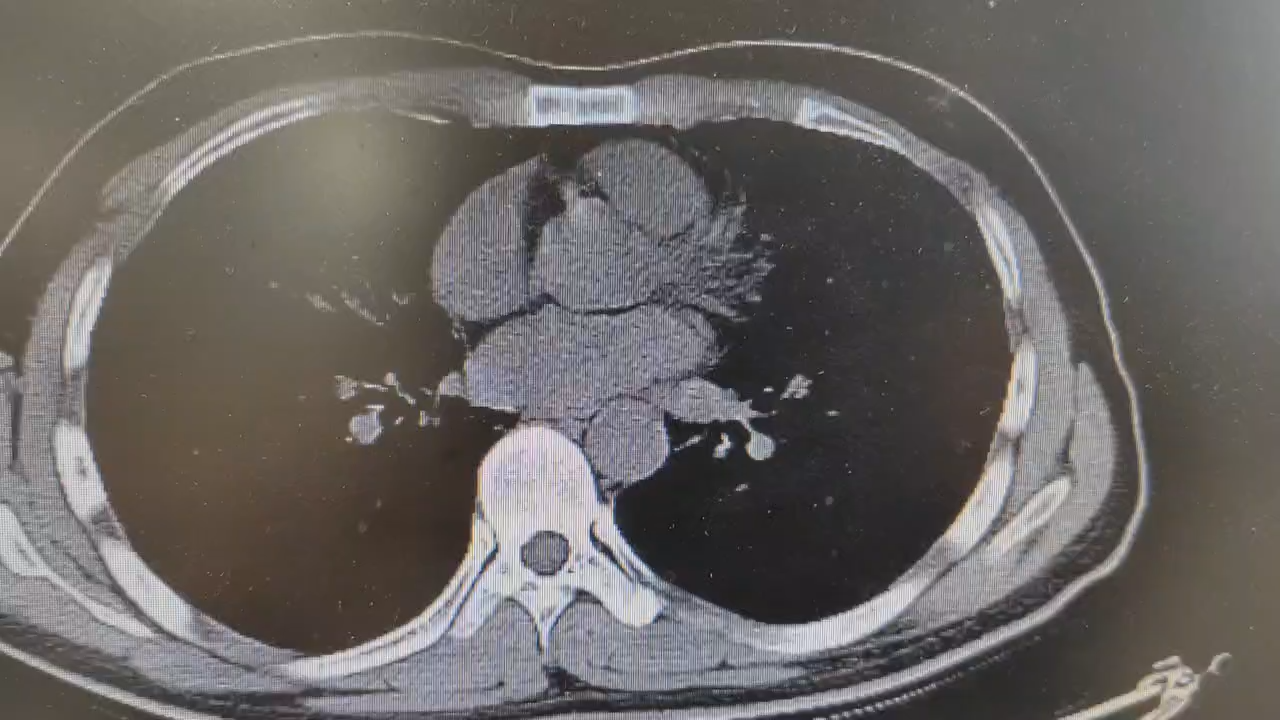

辅助检查:胸部CT:双肺多发磨玻璃影,考虑双肺弥漫性病变,间质性肺炎?病毒性肺炎? 其他?请结合临床随诊复查。血常规+全血超敏C反应蛋白:白细胞6.8x10^9/L、中性细胞比率63.3%、淋巴细胞26.4%、嗜酸性粒细胞比率0.4 %、单核细胞比率 9.8 %;( 超敏C反应蛋白 19.81 mg/L;心肌酶、电解质未见明显异常。

临床诊断:肺炎